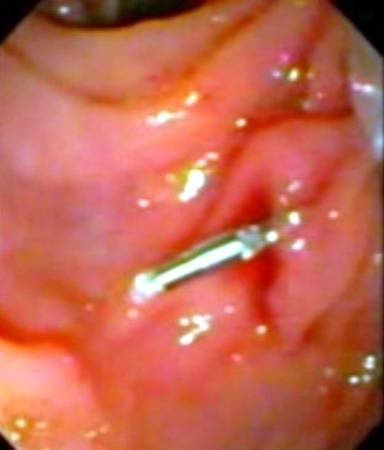

Capsule endoscopy (Given Imaging Ltd., Yoqneam, Israel) was performed after overnight fasting and preparation with polyethylene glycol ingestion and revealed the presence of fresh blood in the proximal jejunum along with a pool of fresh blood with no underlying ulcer (Figure 1). The major papilla was not identified on the capsule endoscopy. A push enteroscopy was subsequently performed which revealed the presence of fresh red blood in the distal duodenum and proximal jejunum. No bleeding lesion was identified. The push enteroscope was immediately withdrawn and a side viewing endoscope (TJF 160, Olympus Optical Co. Ltd., Tokyo, Japan) was inserted. On side view endoscopy, a pool of fresh blood was localized near the papilla (Figure 2). Using a cannula, the area was washed with distilled water and revealed an ooze of fresh blood from a pinpoint defect in the periampullary region. There was no surrounding ulcer or reddish area suggestive of a Dieulafoy’s lesion (Figure 3). Immediate hemostasis was achieved with an endoscopic injection of adrenalin.

Figure 3. Side view endoscope: oozing of fresh blood from a pinpoint defect in the periampullary region, suggestive of a Dieulafoy’s lesion. |